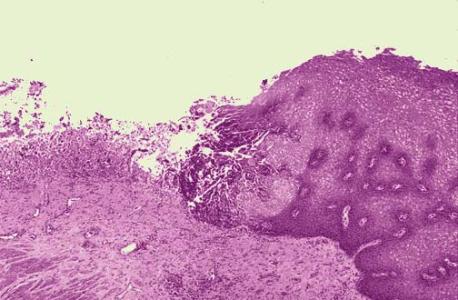

一、棘层松解

由于表皮细胞间桥桥粒及张力细丝等的变性,细胞间失去了紧密的联系而成松解状态,因此形成表皮内的裂隙、水疮或大抱。导致棘层松解的原因有自身免疫因素,如天疱疹。遗传因素引起的棘层松解见于慢性家族性良性天癌疮、毛囊角化病。